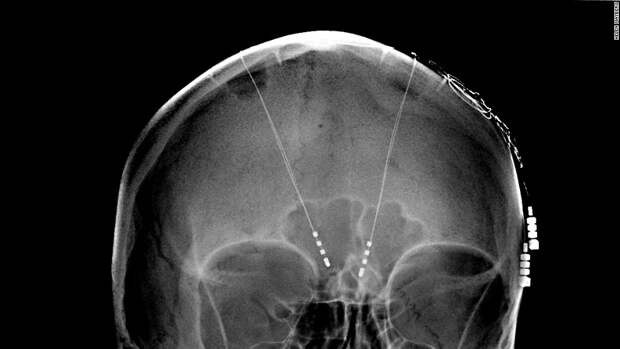

На сегодняшний день около полумиллиона человек используют чипы, подключенные к мозгу. Большая часть из них приходится на имплантаты, используемые для борьбы с глухотой, однако некоторые относятся к устройствам глубокой стимуляции головного мозга (ГСМ), помогающие при болезнях Альцгеймера, Паркинсона и эпилепсии.

Принцип работы имплантатов для ГСМ состоит в подаче электрических импульсов по электродам в определенные участки мозга. В случае пациентов с эпилепсией такие устройства помогают контролировать припадки.